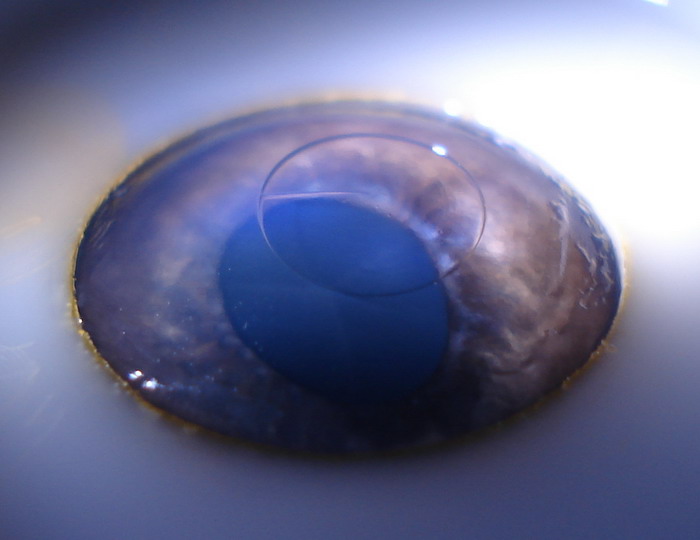

Akis

Ant kiaulės akies ragenos lazeriu nuabliuotas (nugarintas) +10D lęšis.